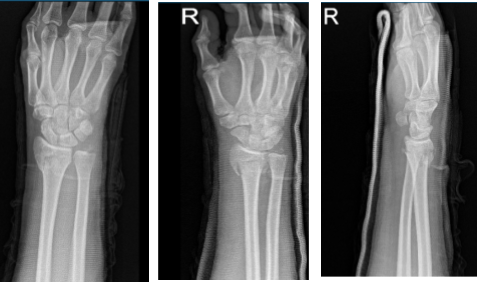

4th week post operative, considering the wires were poking under skin and imminent to break it, we decided to remove the wires and long arm splint to continue. Xray result reviewed.

Right wrist X-ray 3 or more views-4th week post operative